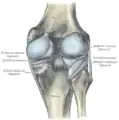

Articulația genunchiului drept, din față, prezentând ligamentele interioare